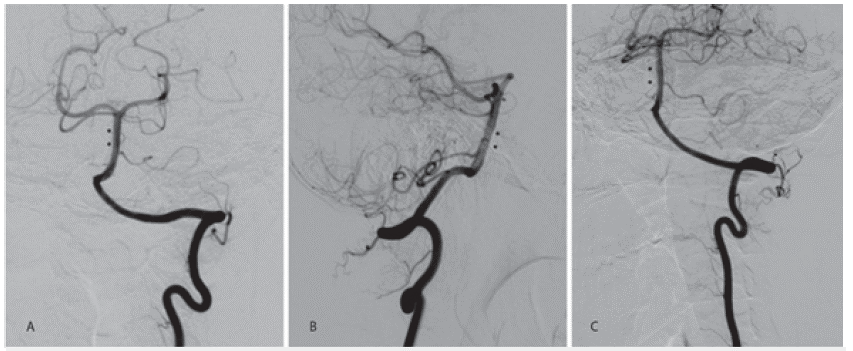

La resonancia magnética nuclear de cerebro con angiografía (RMN) evidencia lesión isquémica aguda en tercio medio lateral izquierdo de la protuberancia (figura 1A y 1B). Secuencias de angiorresonancia: área de estenosis e irregularidad de la pared de la arteria basilar (figura 1C y 1D). La panangiografía cerebral corrobora aneurisma disecante del tercio medio de la arteria basilar de 8,5 mm y cuello ancho (5,8 mm) con zona de estenosis supralesional (figura 2A, 2B, 2C).

IRM de cerebro con angiografía. A. Pequeña imagen hiperintensa en FLAIR que compromete porción lateral izquierda de protubrencia (flecha blanca). B. Secuencia de difusión en la que se observa restricción tisular por lesión isquémica aguda (flecha blanca). C y D. Angiorresonancia vista AP y lateral derecha, estenosis crítica de la basilar con dilatación aneurismática asociada (flechas blancas).

Figura 1: IRM de cerebro con angiografía. A. Pequeña imagen hiperintensa en FLAIR que compromete porción lateral izquierda de protubrencia (flecha blanca). B. Secuencia de difusión en la que se observa restricción tisular por lesión isquémica aguda (flecha blanca). C y D. Angiorresonancia vista AP y lateral derecha, estenosis crítica de la basilar con dilatación aneurismática asociada (flechas blancas).